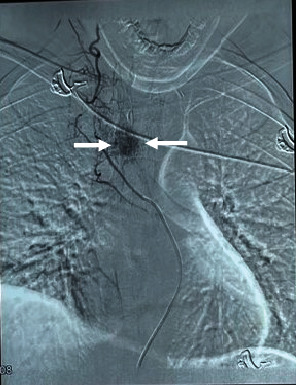

Aggressive thoracic hemangiomas are rare, benign tumors that extend into the spinal canal and cause neurological symptoms. Delayed diagnosis and treatment, due to a paucity of literature on optimal treatment strategies, can increase morbidity. This case report describes a 19-year-old male patient with aggressive thoracic hemangioma who presented with upper back pain and progressive weakness of the lower extremities. The patient underwent preoperative embolization and sclerotherapy, followed by decompression, posterior instrumentation, and stabilization. The final diagnosis was confirmed by biopsy, and there was a significant improvement in neurology after the surgical intervention. The diagnosis of rare lesions, such as aggressive hemangiomas, requires a high level of clinical suspicion and the assistance of imaging modalities in patients with features of compressive myelopathy. A combination of endovascular and surgical approaches can lead to optimal outcomes.